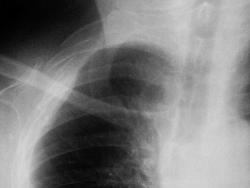

Просто показать.Случается и верхние рёбра ломаются. Женщина. ДТП (падение с велосипеда)

Упала на горизонтальную поверхность или на препятствие типа бардюра? I  ребро кстати не сломано , сломать его как я понимаю, непросто в силу того, что спереди закрыто ключицей, сзади массивом задней группы мышц надплечья (трапецевидной, мышцей поднимающей лоптку и др.) .

Механизма травмы не помнит (Бахус виноват), привезли с улицы. I ребро, действительно целое. Сломаны II-IV р.

В таком случае, снимок лопатки также может быть полезен.

Да и правый плечевой сустав снять не помешало бы, не нравится мне его изображение...

Красивый снимок. Второй раз, что ли, уже упала ) ? Слева тоже старые переломы. Надо в рекомендациях посоветовать транпортное средство поменять )